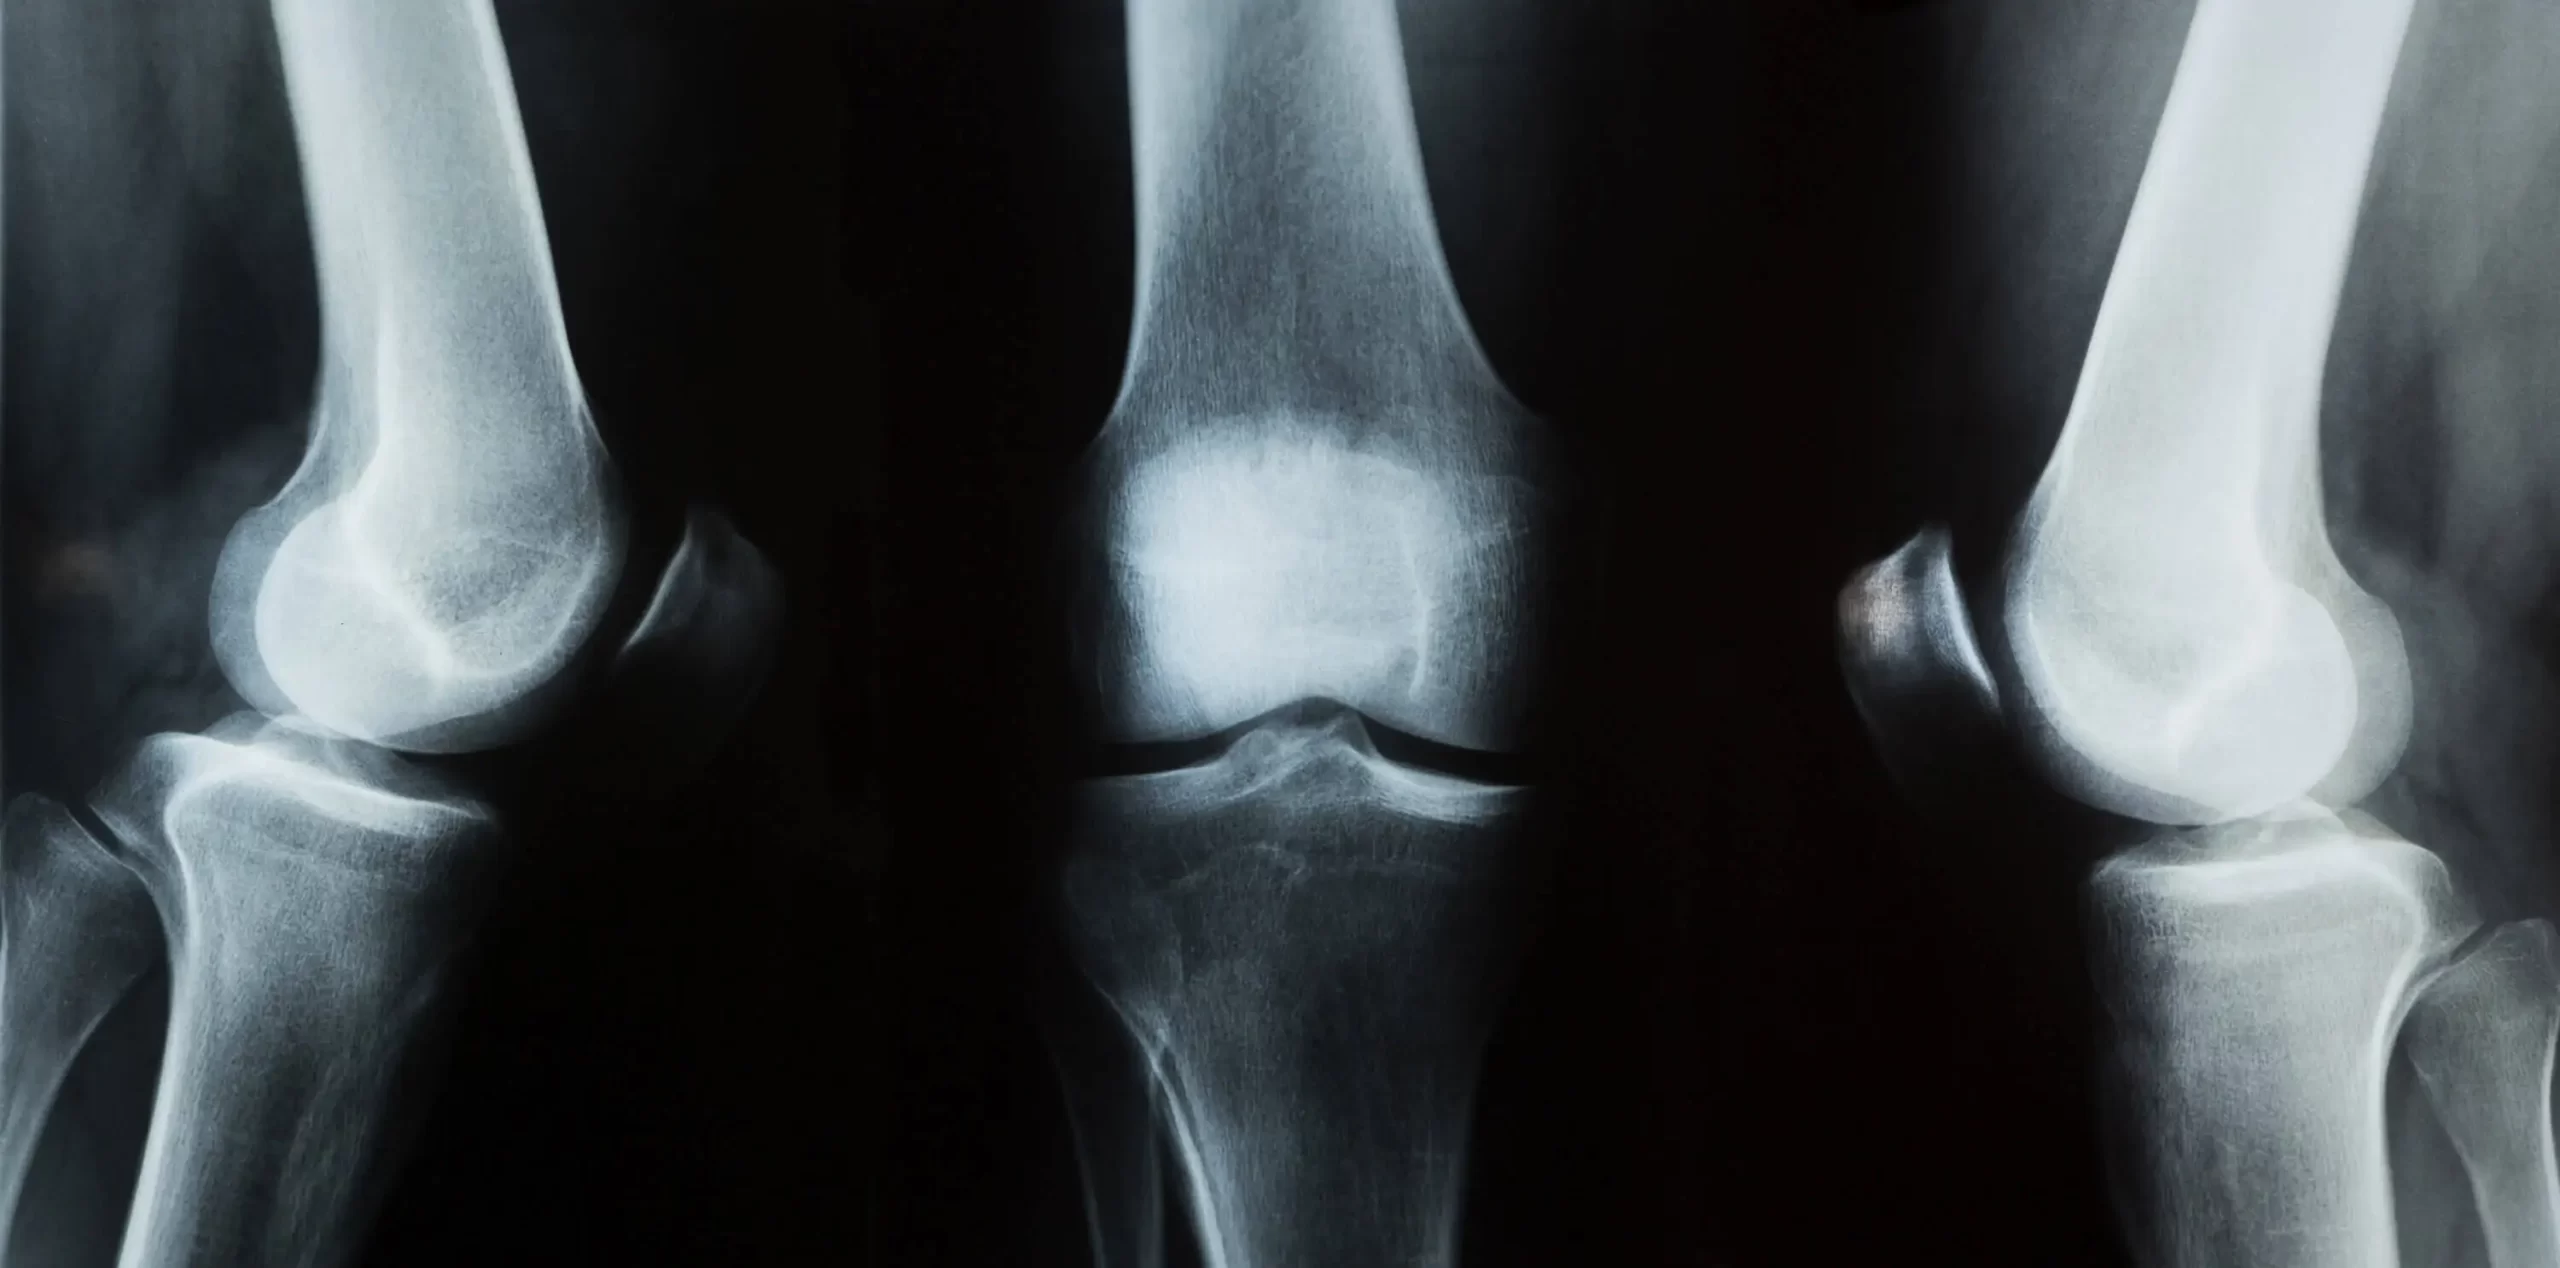

A structure that appears abnormal on an X-ray in an adult may actually be normal in a growing child because certain parts of the bone have not yet fused.

Knowledge of skeletal development helps healthcare professionals interpret imaging correctly and avoid unnecessary concern.